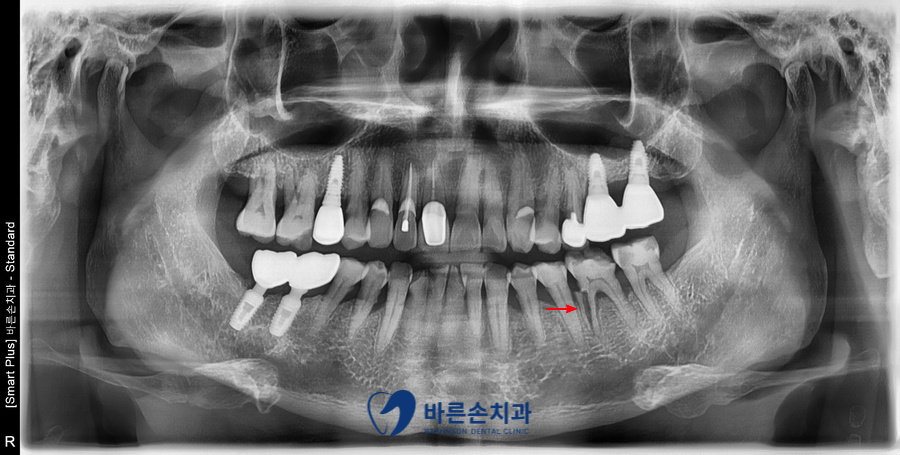

정확한 진단을 위해 파노라마 X-ray를 찍어 보았는데요.

빨간색 화살표 있는 부분의 치아를 보시면

어금니 치아 뿌리가 수직으로 파절되어있는 것을 확인할 수가 있습니다.